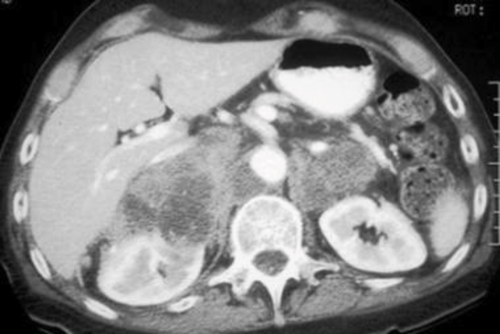

A 45-year-old man undergoes a CT of his abdomen to stage a newly diagnosed bowel malignancy.

An enlarged right adrenal gland, with a smooth contour and homogenous appearance.

Smooth, homogenous solitary lesion <4cm with <10HU (i.e. lipid rich), with >60% contrast washout.

An MRI scan is as effective as CT for detecting benign from malignant lesions. Non-functional adenoma on T2 imaging have the same density as the liver, with rapid washout of contrast. Malignant lesions show intermediate to high density on T2 imaging, with rapid and intense enhancement.

Risk of malignancy is 1%, but given the fact that he has a history of bowel cancer this increases to 75%. Therefore 25% risk it is benign.